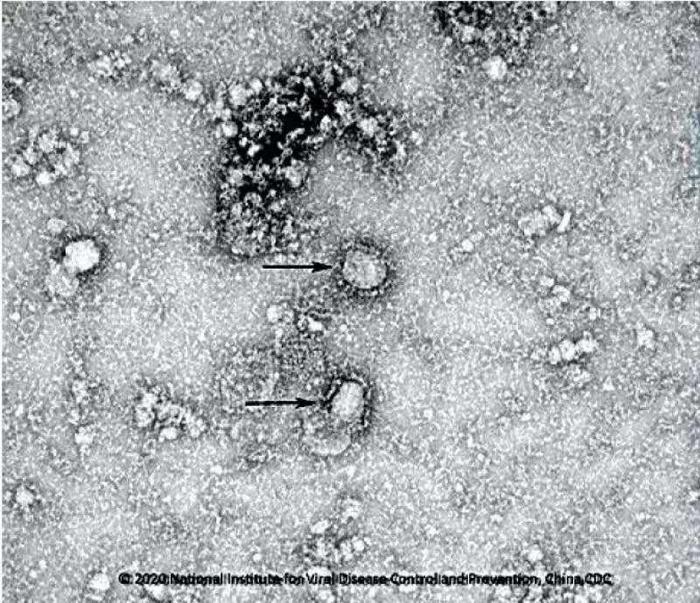

[经济日报]国家病原微生物资源库公布首株新型冠状病毒毒种信息。图片来源:中国疾控中心网站

[经济日报]国家病原微生物资源库公布首株新型冠状病毒毒种信息。据中国疾控中心网站消息 , 为做好新型冠状病毒感染的肺炎疫情防控支撑工作 , 发挥国家病原微生物资源库科技资源共享服务职能 , 国家病原微生物资源库于1月24日发布了由中国疾病预防控制中心病毒病预防控制所成功分离的我国第一株病毒毒种信息及其电镜照片、新型冠状病毒核酸检测引物和探针序列等国内首次发布的重要权威信息 , 并提供共享服务 。